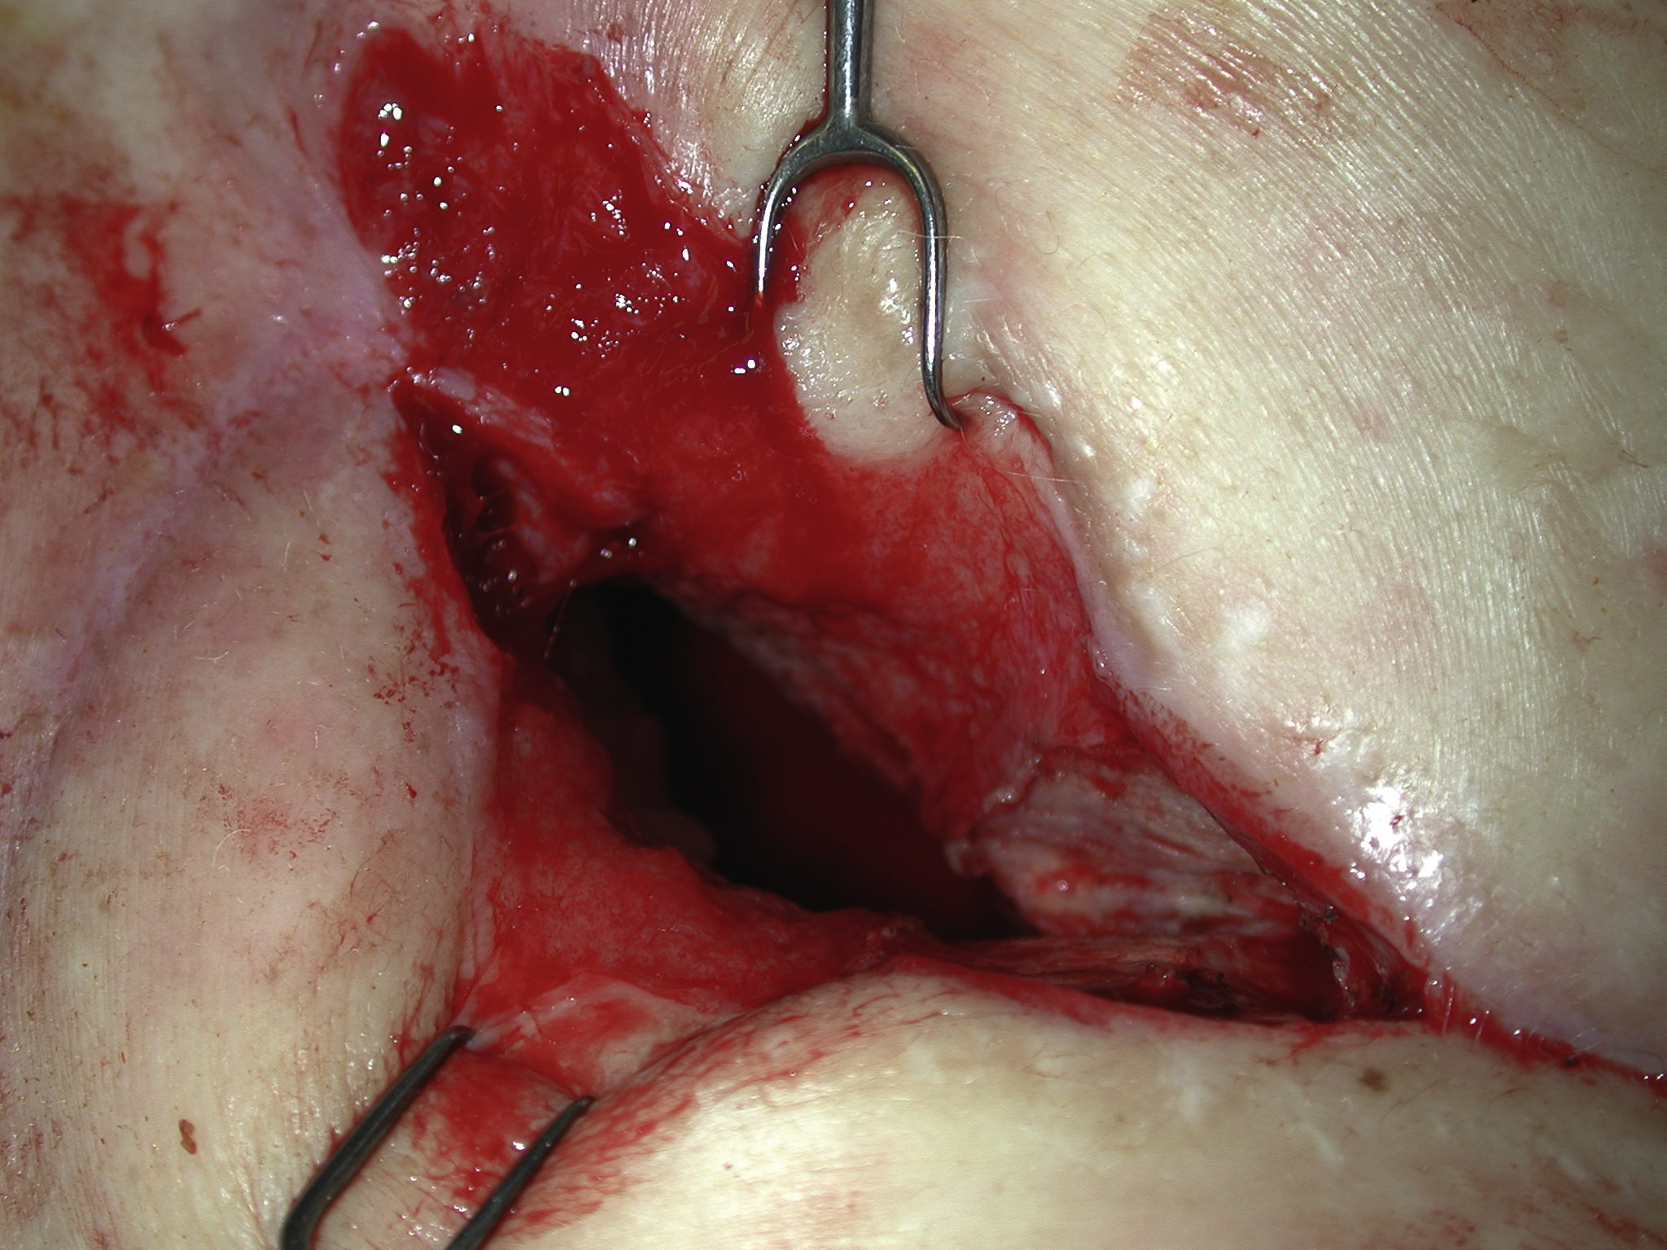

She unfortunately developed recurrent bronchopleural fistula about 4 months after the first flap surgery, with a small open wound on her right chest and a persistent air leak. She was otherwise doing well with no evidence of infection ( Fig. 24.7 ). Repeated chest CT scans showed a less optimal filling of the pleural cavity ( Fig. 24.8 ). At this point, it became clear that additional well-vascularized tissue would be required not only to seal the recurrent bronchopleural fistula but also to obliterate the remaining dead space within the thoracic cavity. She was brought to the operating room for the second intrathoracic flap transfer. During exploration, the recurrent bronchopleural fistula was identified ( Figs. 24.9 and 24.10 ) and repaired again by the thoracic surgery service with additional suture and fascial patch graft ( Fig. 24.11 ). Because of the previous right thoracotomy, the left latissimus dorsi myocutaneous flap was selected and elevated as a free flap ( Fig. 24.12 ). The right thoracodorsal vessels were explored for the recipient vessels. After successful end-to-end microvascular anastomoses for both artery and vein, the entire flap appeared to be well perfused ( Fig. 24.13 ). The de-epithelialized flap could be placed freely anywhere inside the pleural cavity. The repair site of the recurrent fistula was covered with the muscular portion of the flap and the remaining dead space was completely obliterated by the flap with the de-epithelized portion facing out ( Fig. 24.14 ). With concerns of the flap being buried inside the chest, it was observed for an hour in the operating room after both microvascular anastomoses before the chest wound was closed. It reassured the surgeon that both microvascular anastomoses were patent and there were no technical errors in the free tissue transfer. The chest wound was closed again in two layers after local tissue rearrangement ( Fig. 24.15 ). The patient tolerated the entire procedure well and was extubated the next day. She was found to have no further air leak after the second flap surgery and was discharged from the hospital 2 weeks postoperatively